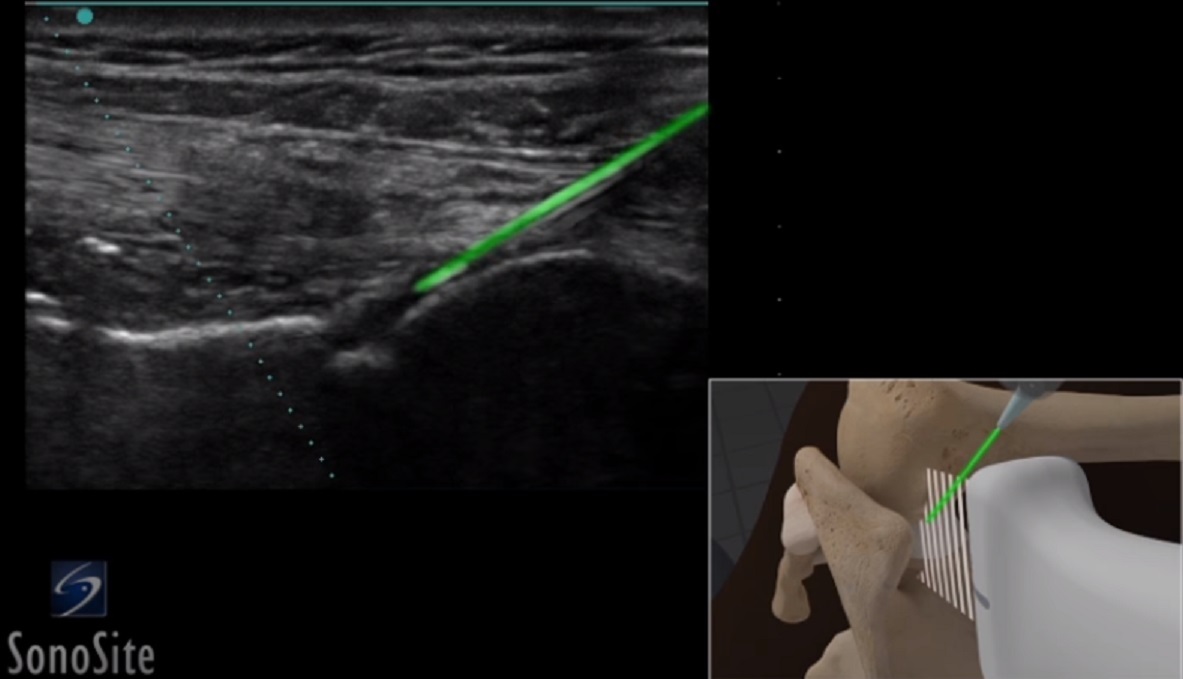

肩甲上腕針画像